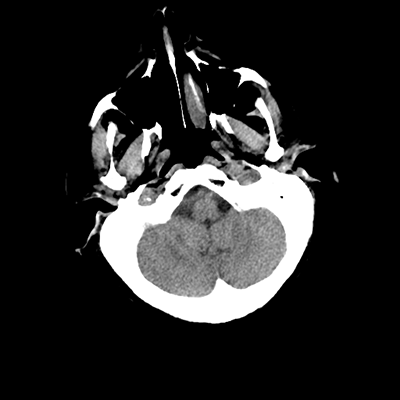

An 76 year-old man with HTN, CAD s/p PCI (two years prior), and PAD initially presented to the ED with subacute left hemiparesis and gait difficulties. He was found to have a large right frontal tumor. He was admitted to the NCCU, and then undergoes a craniotomy for tumor resection later in the week. A post-op head CT is obtained.

There are expected post-operative changes, along with some scant hemorrhaging along the posterior and inferior aspects of the surgical bed. We'll want to ensure that this hemorrhage is stable with a repeat scan, at which point we can start DVT chemoprophylaxis-- will end up being between 24-48 hours post-op.